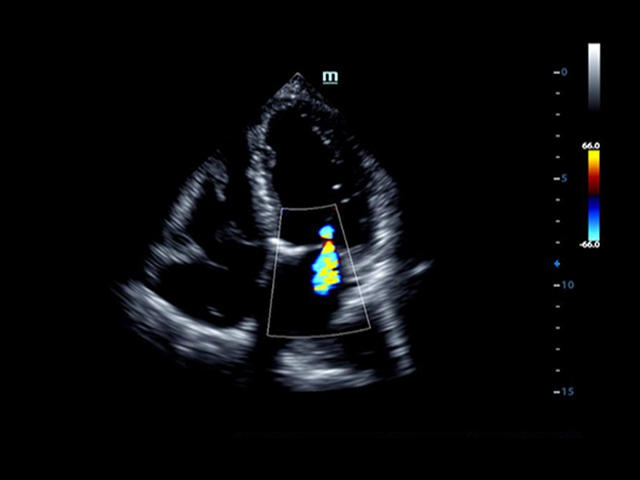

• LVO - опция проведения исследования левого желудочка с применением контрастных веществ

• LVO - опция проведения исследования левого желудочка сердца с применением контрастных веществ;

Кардиология:

Да